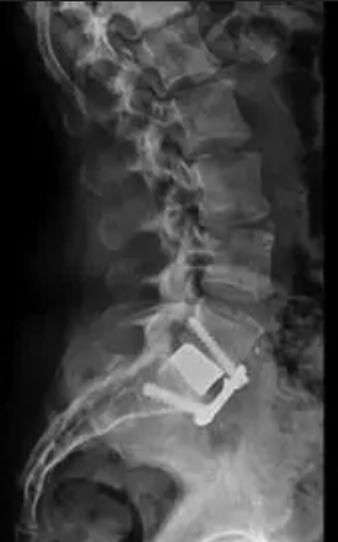

After Surgery Results

Oblique Lumbar Interbody Fusion – performed from the side, avoiding major back muscles and reducing tissue damage while providing excellent disc space access.

The surgeon removes the damaged disc or diseased bone, places a cage or bone graft between the vertebrae, and secures it with screws and rods. Over months, the bones heal together naturally. The surgical approach (front, back, or side) depends on the patient's specific condition and body type.